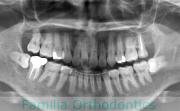

No.22V-029

- 叢生

- 上顎前突

- 19歳

- 男性

- 上:

- 8448

- 下:

- 主な使用装置:

- FEA 022

- 治療にかかった費用:

- 92万円

でこぼこを治したいということで来院されました。上下左右から親知らずも第一小臼歯も抜歯が必要で、歯科矯正アンカースクリューを併用して大臼歯を後ろに引っ張りながらの治療でした。3年弱、35回程度の通院が必要でした。

叢生が著しく、後戻りのリスクがあります。またアンカースクリューが必須のため、もしもスクリューが安定しないと、治療が難しく長くなってしまう恐れがありましたが、幸い脱落は見られませんでした。